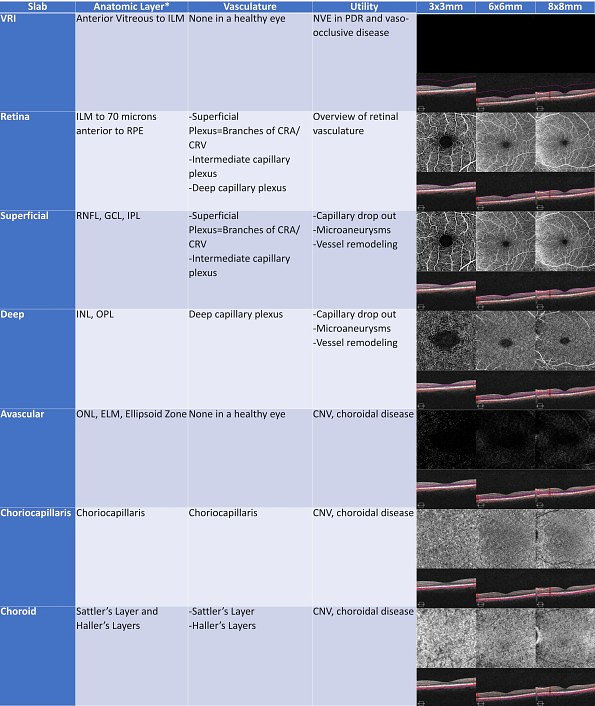

To make it easy for our readers, I have added my standard reference of the various OCT-A enface slabs in 3x3mm, 6x6mm, and 8x8mm.

Figure 2: A standard reference of the preinstalled OCT-A enface slabs in 3x3mm, 6x6mm, and 8x8mm scans.

*Estimated anatomic layer

ILM: internal limiting membrane; NVE: neovascularization elsewhere; PDR: proliferative diabetic retinopathy; RPE: retinal pigment epithelium; RNFL: retinal nerve fiber layer; GCL: ganglion cell layer; IPL: inner plexiform layer; INL: inner nuclear layer; OPL: outer plexiform layer; ONL: outer nuclear layer; ELM: external limiting membrane; CNV: choroidal neovascularization

Though it is possible to create custom enface slabs, the many preinstalled Angioplex enface slabs are highly diagnostic in the multitude of vascular conditions, rendering customization virtually unnecessary. Each prebuilt slab has its own purpose and is a unique tool in the clinician’s armamentarium. The prebuilt enface slabs are fairly consistent over a wide range of patients, allowing for easy comparisons between two angiograms. As with structural OCT scans, the ZEISS CIRRUS is able to align two scans from different days to facilitate side-by-side analysis.